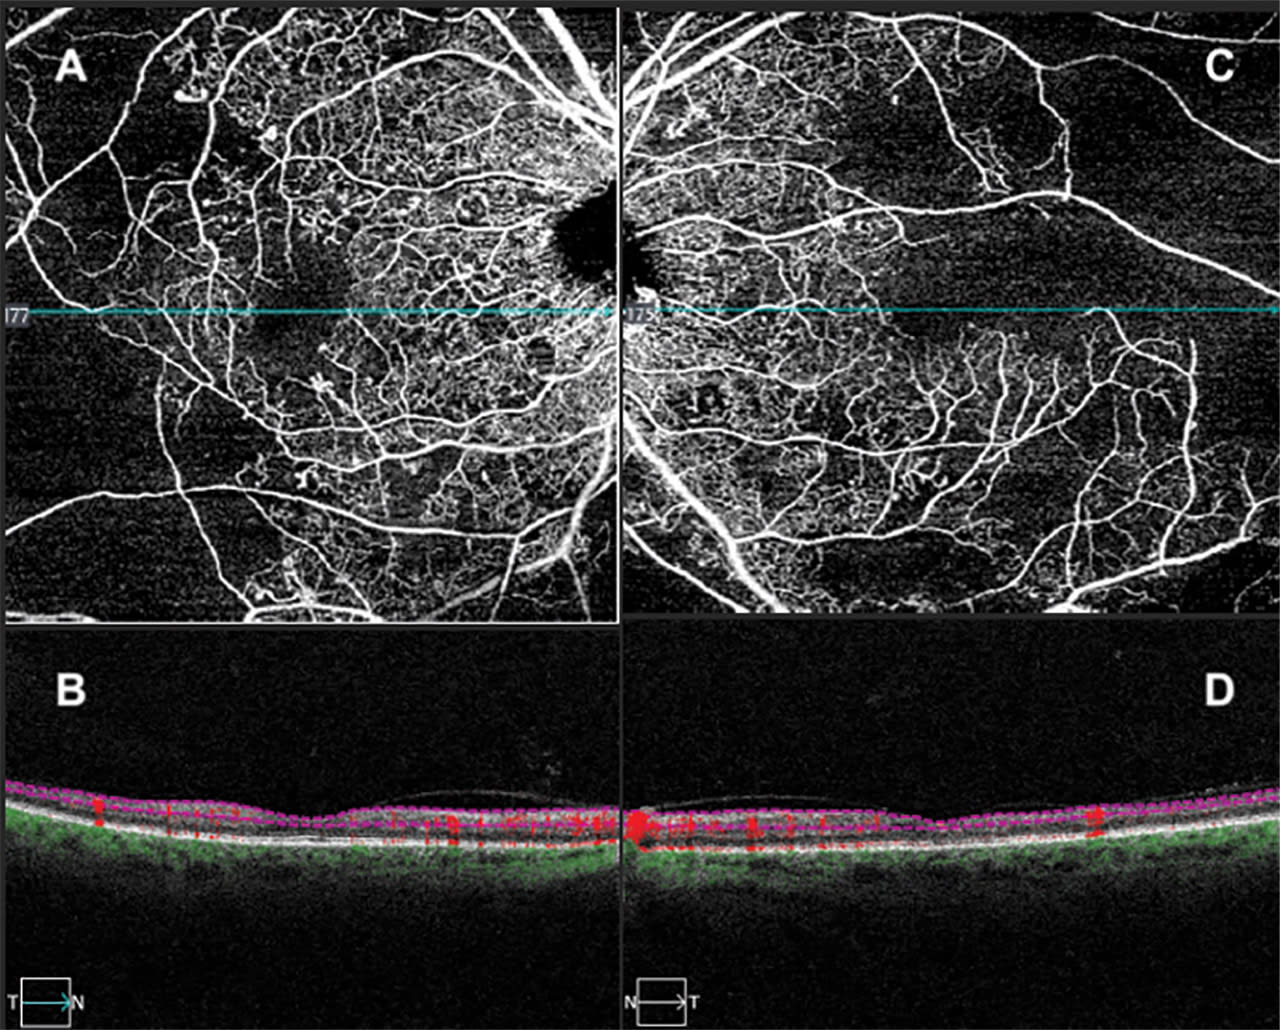

Figure 1. In a 55-year-old male with diabetic retinopathy, swept-source optical coherence tomography angiography 6x6 mm scans show an enlarged, irregular foveal avascular zone demonstrating ischemic maculopathy as well as profound capillary dropout in the superficial plexus of the right eye (A, B) and left eye (C, D).

OCTA can be used to evaluate a wide variety of ophthalmic conditions that affect the retinal vasculature, choriocapillaris, and choroid. These include non-neovascular and neovascular age-related macular degeneration (AMD), diabetic retinopathy, retinal vein occlusions, central serous chorioretinopathy (CSCR), macular telangiectasia, and choroidal neovascularization (CNV) due to other retinal diseases such as myopic degeneration. For AMD, OCTA can be used to visualize areas of macular neovascularization (MNV) at different segmentations.5,6 When evaluating diabetic retinopathy, OCTA offers the ability to assess for microaneurysms, neovascularization, areas of retinal nonperfusion, and changes to the foveal avascular zone.7 Furthermore, the advent of widefield OCTA, similar to widefield fluorescein angiography (FA), has been shown to have comparable results in the detection of peripheral retinal nonperfusion and areas of neovascularization.8,9 In addition, OCTA can be used to evaluate areas of capillary nonperfusion in conditions such as branch retinal vein occlusions (BRVO), central retinal vein occlusions (CRVO), branch retinal artery occlusions (BRAO), and central retinal artery occlusions (CRAO).5 Overall, OCTA serves as a valuable noninvasive modality for assessing common retinal diseases in the clinical setting.